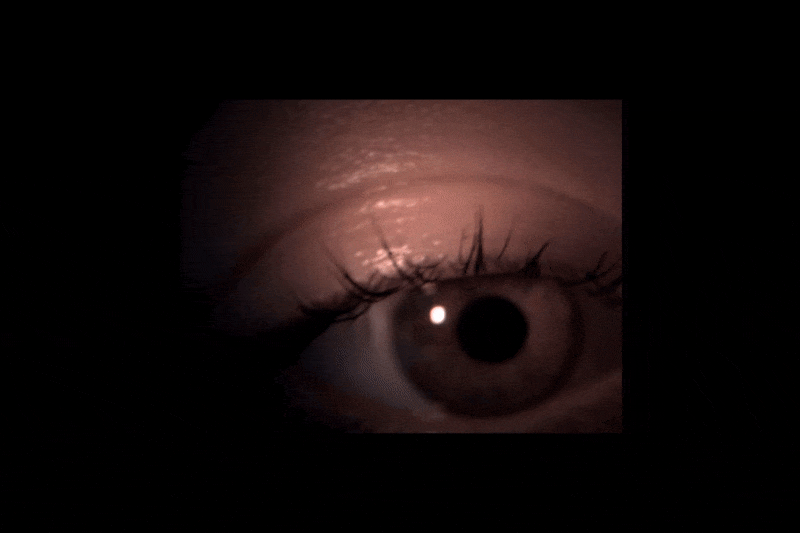

Virtuálna prehliadka vyšetrenia z očnej optiky na dvoch rozdielnych prístrojoch. Čo vidí optometrista, kým my sledujeme svetlo z prístroja? Čo z daného obrazu vie vyčítať? Čo všetko dokážu tieto prístroje? Klient môže prvýkrát vidieť postup vyšetrenia ,,očami lekára" prostredníctvom prehliadky prednej a zadnej časti oka s rozkliknuteľnými definíciami.